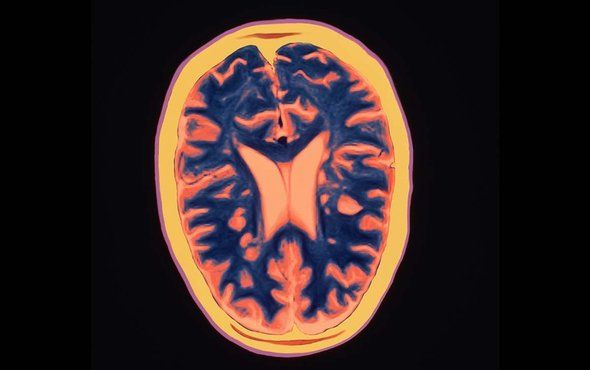

İki farklı bilim insanı grubunun yürüttüğü çalışmalar sonucunda, bağışıklık sisteminin nöronları kaplayan miyelin kılıfa saldırmasıyla titremeye, yorgunluğa, bilişsel sorunlara ve daha fazlasına sebep olan MS (multipl skleroz) hastalığının oluşumunda bağırsak bakterilerinin bir rolü olduğunu gösteren güçlü deliller bulundu.

11 Eylül 2017’de sunulan bir çalışmanın sonuçlarına göre, MS hastalarında oldukça fazla bulunan bağırsak bakterilerinin beyaz kan hücrelerini, nöronlar da dahil vücudun kendi hücrelerine saldırmaya daha meyilli olacak şekilde değiştirdiği ortaya çıktı. Bir diğer deneyde ise tek yumurta ikizlerinden oluşan bir grup farenin bir kısmına MS’li hastalardan; diğer kısmına ise sağlıklı ikizlerinden alınan bağırsak bakterileri aktarılmıştır. MS’li hastaların bağırsak bakterilerini taşıyan farelerin, diğer gruba kıyasla, MS hastalığına yakalanma olasılığının arttığı görülmüştür.

Bağırsak bakterilerinin nöronları etkileyebilmesi kulağa garip gelse de bu konudaki kanıtlar giderek artıyor. Hatta bu kanıtlar o kadar fazla ki, uluslararası bir konsorsiyum kendini, hangi bakterilerin MS’i ilerlettiği, hangilerinin hastalığı önlediğini anlamaya adamış durumda. Yeni çalışmalar da MS hastalığı ve mikrobiyom arasındaki bağlantıyı güçlendirecek nitelikte.